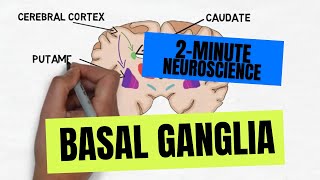

2-Minute Neuroscience: Basal Ganglia

2-Minute Neuroscience: Basal Ganglia Neurology | Basal Ganglia Anatomy & Function | Direct & Indirect Pathways

2-Minute Neuroscience: Basal Ganglia

2-Minute Neuroscience: Basal Ganglia Neurology | Basal Ganglia Anatomy & Function | Direct & Indirect Pathways